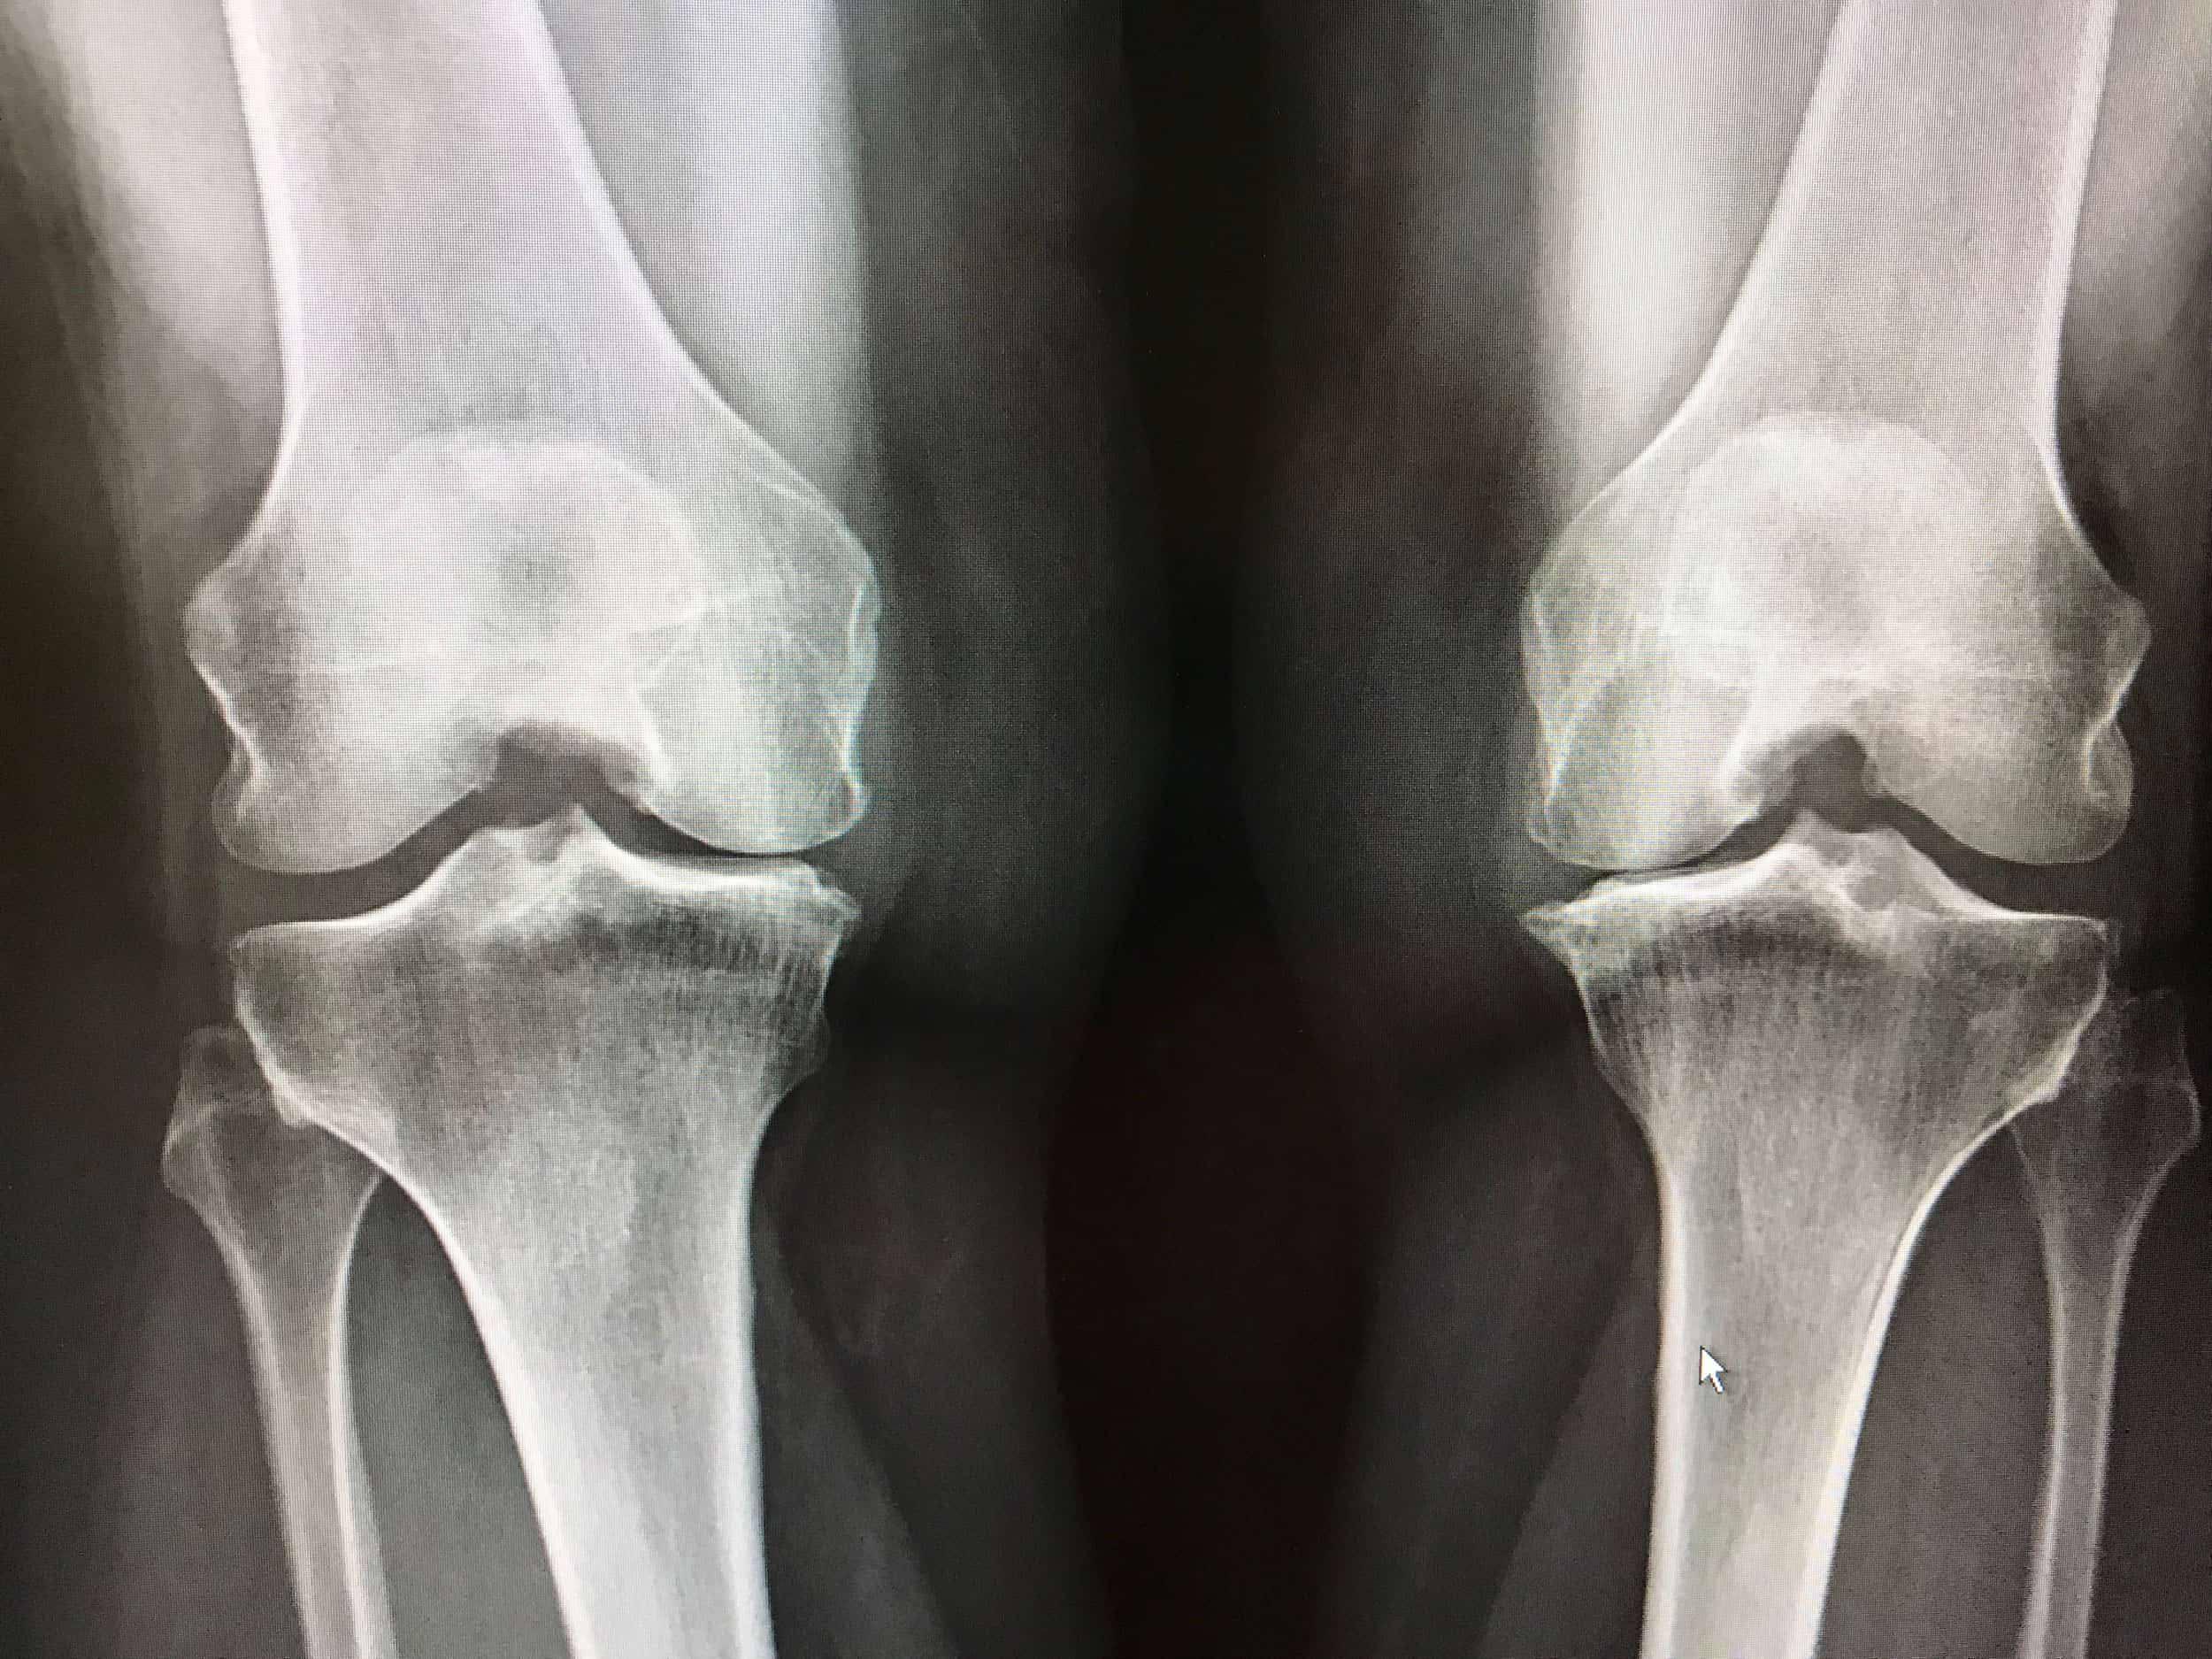

Monter les escaliers devient difficile, la marche plus lourde, et les activités sportives que vous aimiez se transforment en épreuve. L’arthrose du genou, aussi appelée gonarthrose, est une pathologie fréquente qui touche de nombreuses personnes, sportifs ou non. Elle résulte d’une usure progressive du cartilage et provoque douleurs, raideurs et parfois gonflements.

L’arthrose du genou se développe suite à une usure progressive du cartilage qui recouvre les surfaces articulaires. Plusieurs facteurs contribuent à cette dégradation :

L’arthrose n’est pas une fatalité liée uniquement à l’âge. Elle est souvent le résultat d’un ensemble de facteurs mécaniques et biologiques.